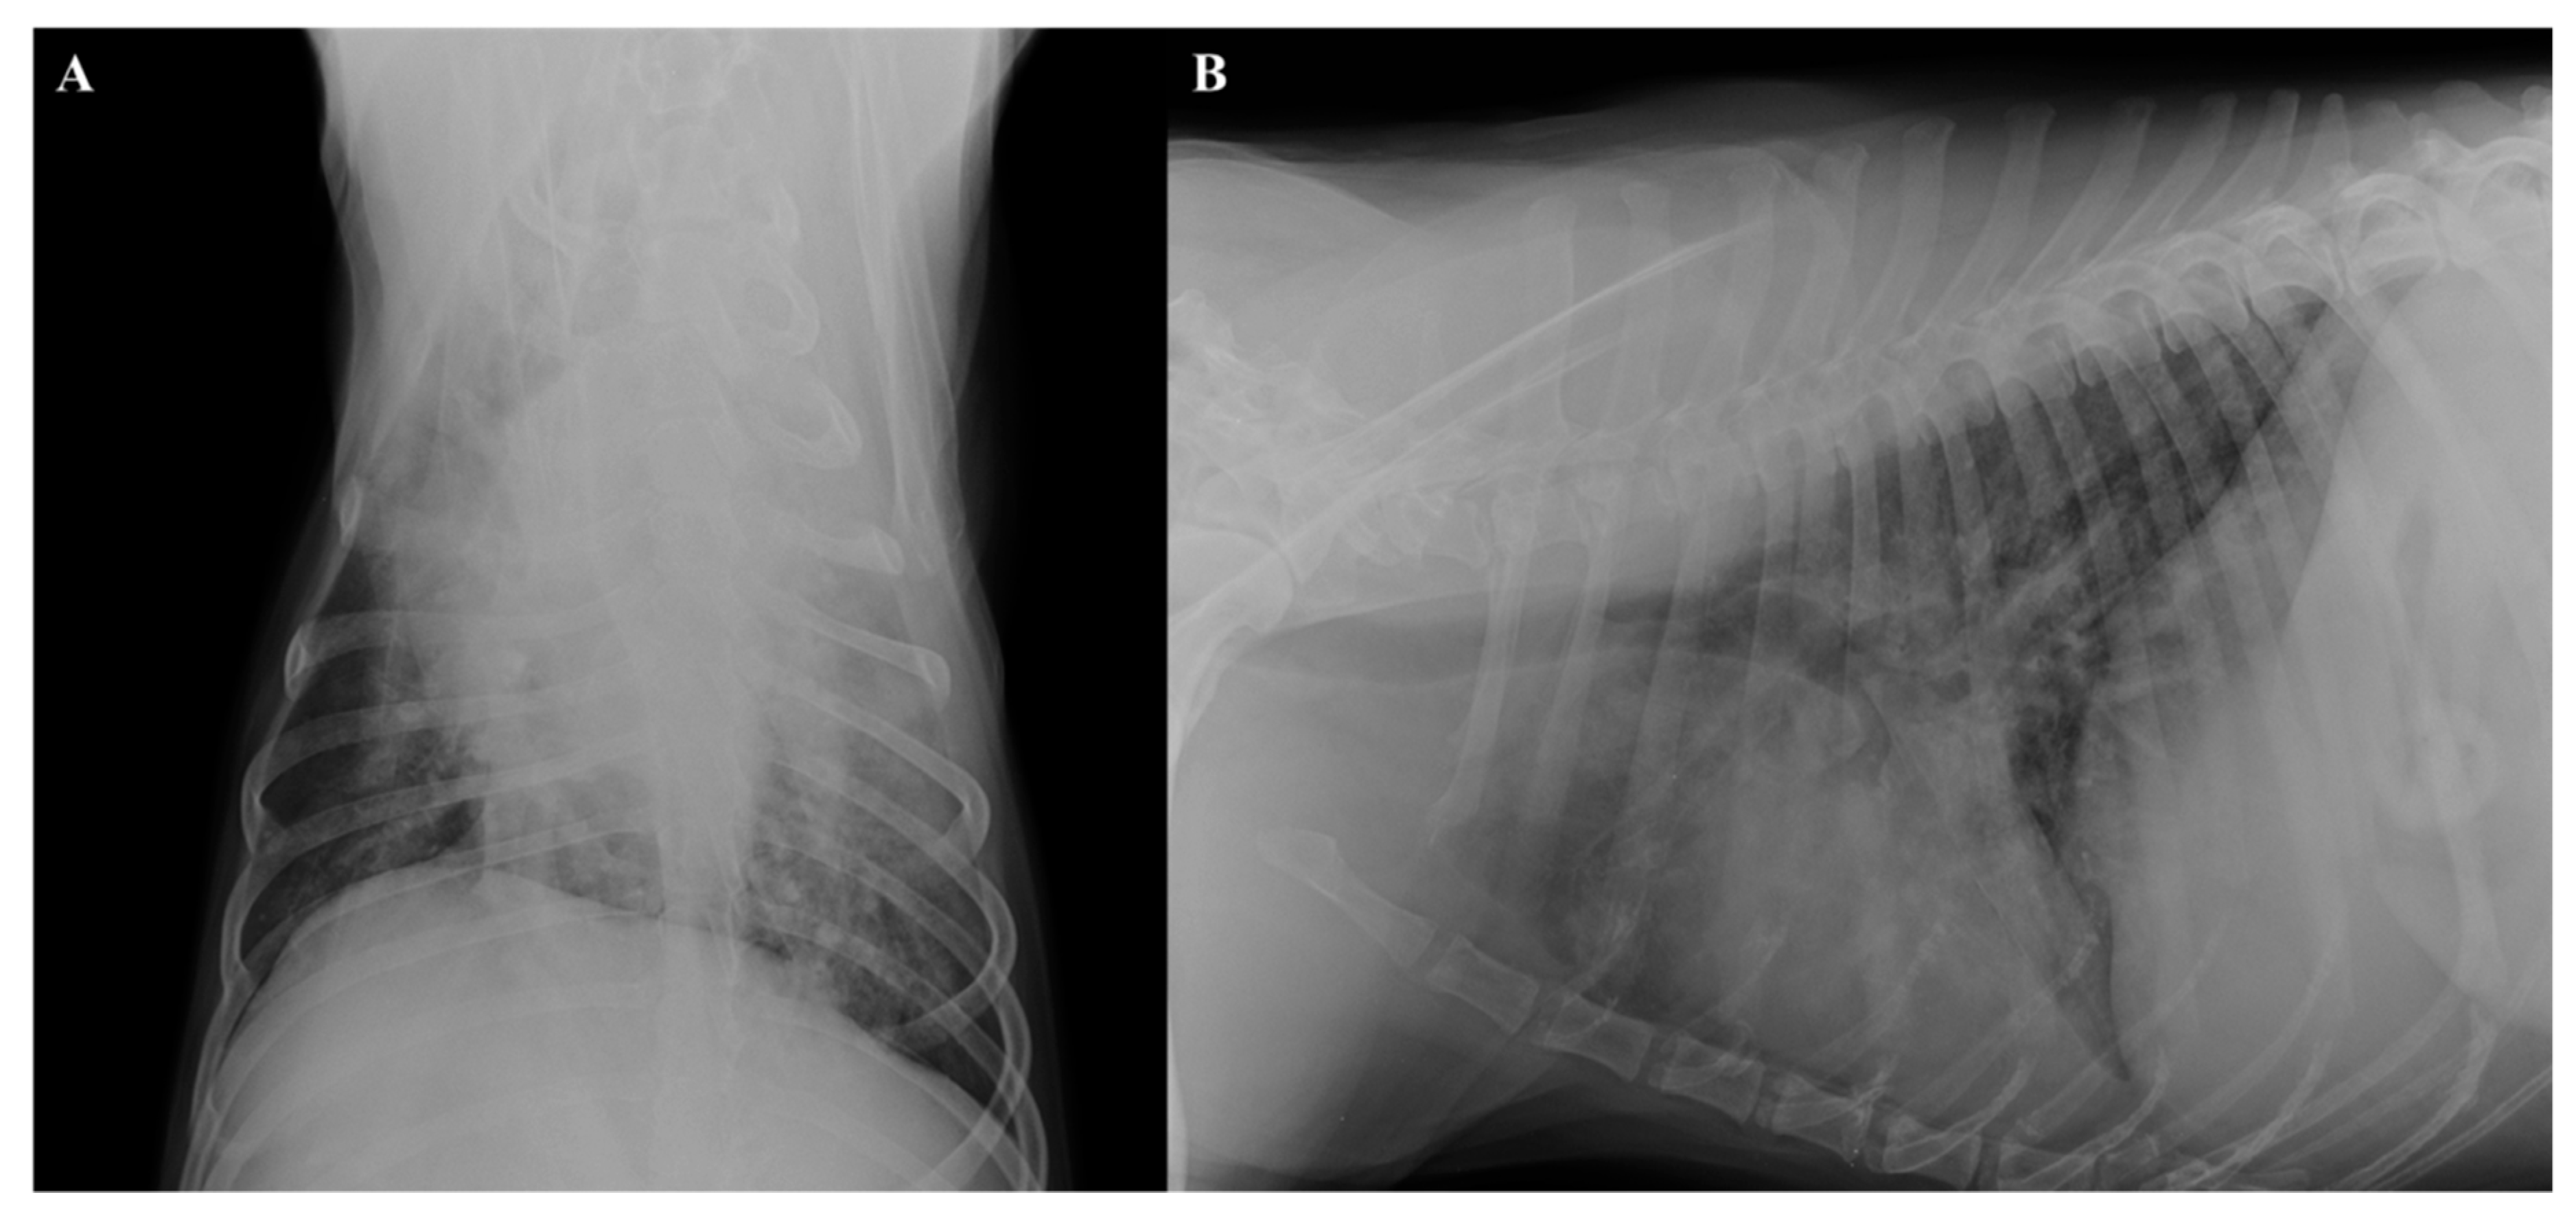

2.2. Radiographic and Ultrasound Examinations